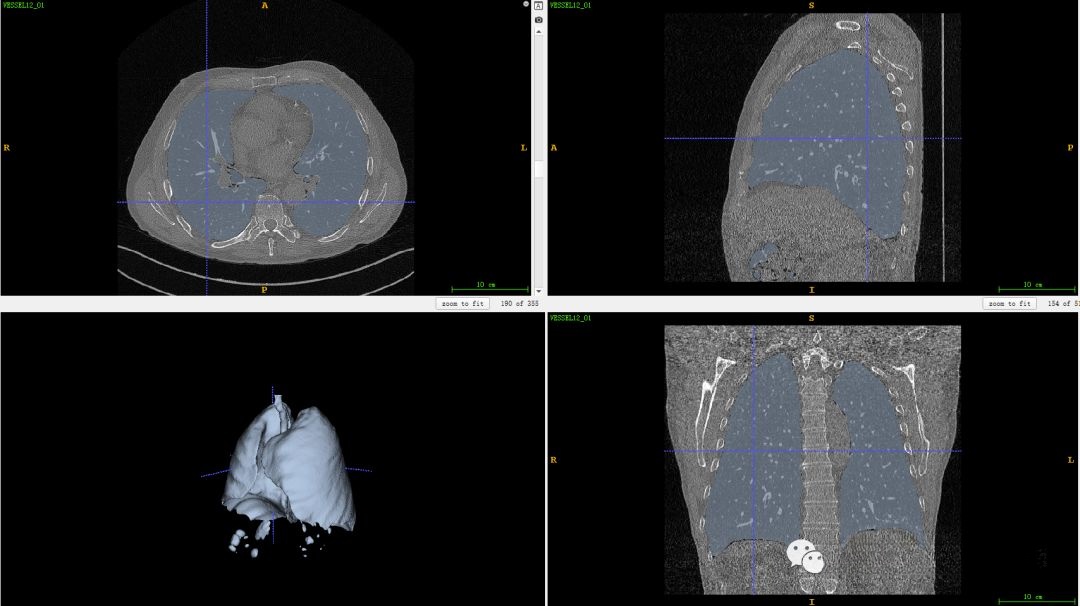

今天用到的数据源自公开发布的VESSEL12《VESsel SEgmentation in the Lung 2012》数据集。该挑战赛旨在通过使用自动或半自动的方法从肺部CT扫描图像中提取出肺动脉区域的影像图谱。然而,在该挑战赛提供的数据集中仅包含原始CT扫描图像及其对应的肺部区域Mask图象。更多详细信息可参考原文链接

二、VESSEL12的肺分割

在本案例中,我们可以直接调用挑战赛提供的Mask来省略这一步骤的处理。而在本案例中,则对之前的医学图像处理案例(一)——基于CT图像的肺分割进行了深入分析与拓展研究,在这一过程中主要包含了六项关键步骤:首先,在观察图像时会发现存在一定的噪声干扰,并通过应用中值滤波器来去除这些噪声影响;其次,在进行图像分割时采用了大津阈值法作为主要手段;第三步则是对背景目标进行识别并予以剔除;第四步则重点进行了对噪声信息的尽量去除;第五步是对肺部轮廓边缘进行重构;第六步则最终实现了肺部组织区域的提取与确定。

三、VESSEL12的肺部气管分割提取

之前文章也说过可以采用Hessian矩阵来增强血管区域,医学图像处理案例(六)——生成血管三维模型所以这里利用Hessian矩阵是多维变量函数的二阶偏导数矩阵,根据其特征值的属性来检测管状类的结构,例如三维Hessian的特征值有lambda_1,lambda_2和lambda_3。 明亮的管状结构有 低的lambda_1和大的lambda_2和lambda_3负值。 相反, 暗管状结构时lambda_1值较低,lambda_2和lambda_3的正值较大。 明亮的板状结构具有较低的lambda_1和lambda_2值以及较大的lambda_3负值。暗的板状结构具有较低的lambda_1和lambda_2值以及较大的lambda_3正值。明亮的球形(斑点)结构具有所有三个特征值都是较大的负数。暗的球形(斑点)结构将具有三个特征值都是较大的正数。所以我们可以通过选择特征值来增强气管区域。 增强后的气管区域还需要阈值分割处理,如下图所示。

最后,我们将该区域与原始图像进行结合,生成肺部气管三维模型结果。